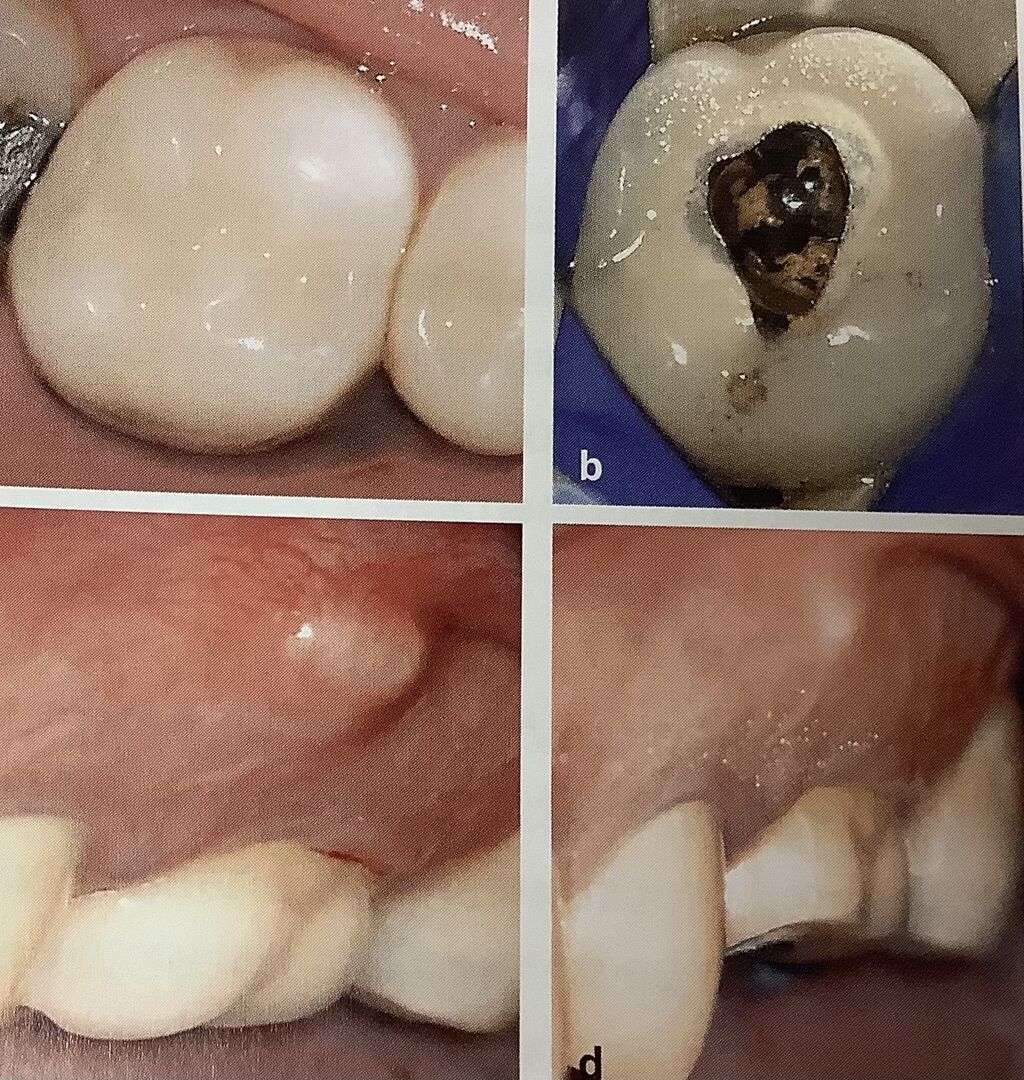

メタルボンドに穴を削る時です。

削る時にセラミックが欠けてしまい、壊れてしまうことがあります。

左のメタボンを外さずに、穴を開けて根管治療をしようとしましたが、

セラミックが欠けてしまいました。

下も左が治療前で、腫れていますね。

で、右が欠けてしまった絵です。

セラミックの部分は

ダイアモンドのバーで高速で水をたっぷりかけながら削るんですが、こんなリスクは付きものです。

超音波の器具もセラミックが欠ける危険があります。

細くて小さな器具を使って行う必要があります。

治療前にその危険、欠けるかもしれないって事を患者さんに説明しておかないと、

後でトラブルになりますね。